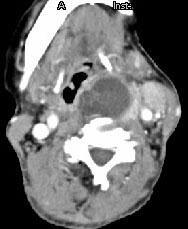

问题 女,64岁,发现双甲状腺肿大一月余,CT如图所示,最可能诊断为 ( )

选项 A、甲状腺转移瘤 B、甲状腺结核 C、甲状腺腺瘤 D、甲状腺癌并淋巴结转移 E、结节性甲状腺肿

答案 D